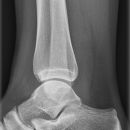

Sprunggelenk seitlich

Malleolus fibularis steht etwa 1cm weiter dorsal und reicht 1,5cm weiter nach kaudal als der mediale Malleolus. Malleolen, abgesehen von ihrer Längendifferenz, exakt übereinander projiziert?

Beurteilungskriterien

• Malleolen exakt übereinanderprojiziert?

• Gelenkspaltweite in der seitlichen Aufnahme gleichmäßig weit?

• Weichteilschwellung ventral des Gelenkspaltes?

• Gelenkstellung des Talus in der Malleolengabel

• Target areas häufiger subtiler Frakturen:

• Kontur der Malleolen und Malleolarspitzen

• posterolaterale Tibiakantenabscherungen (Volkmann-Dreieck)

• Kanten der Trochlea tali (Flake-Frakturen bei bis zu 7% der OSG-Distorsionen!)

• Talushals, Processus posterior tali

• Cave : akzessorische Knochen (Os trigonum, Os supratalare, Os supranaviculare, Os tibiale externum)